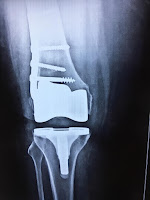

Total Knee Replacement with Fracture Plate

Finally, the X-Ray of her knee taken in

March 2018 showed that the two bones of her knee joint, femur and tibia, were

almost in contact with each other. The joint space, which represents the

cartilage in healthy knees, was almost gone. Ms. Lalita’s pain was unbearable.

But there was a major problem. The plate in

her thigh would obstruct TKR surgery.

He examined the

case and did some research on it and finally came with a solution. He would do TKR

without touching the previously fitter metal plate! He explained what he